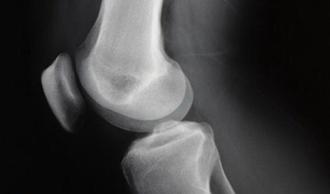

Dolor que aparece al rozar la zona superior de la rótula con la zona inferior del fémur (cóndilo lateral).

Se produce por una deficiente técnica de carrera, frecuentemente inducida por problemas congénitos (comúnmente denominados 'rótula alta').